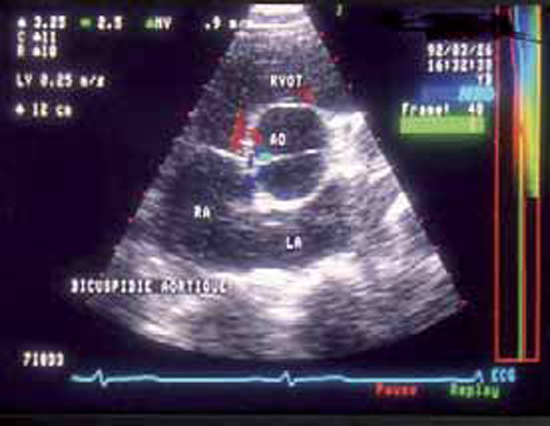

Figure 3 : VG dilaté en écho-TM

Le diamètre télédiastolique du VG atteint 68 mm, le diamètre télésystolique demeure normal à 36,7 mm. La fonction systolique est normale, avec un pourcentage de raccourcissement de 46 % et une fraction d’éjection (FE) de 76 %.